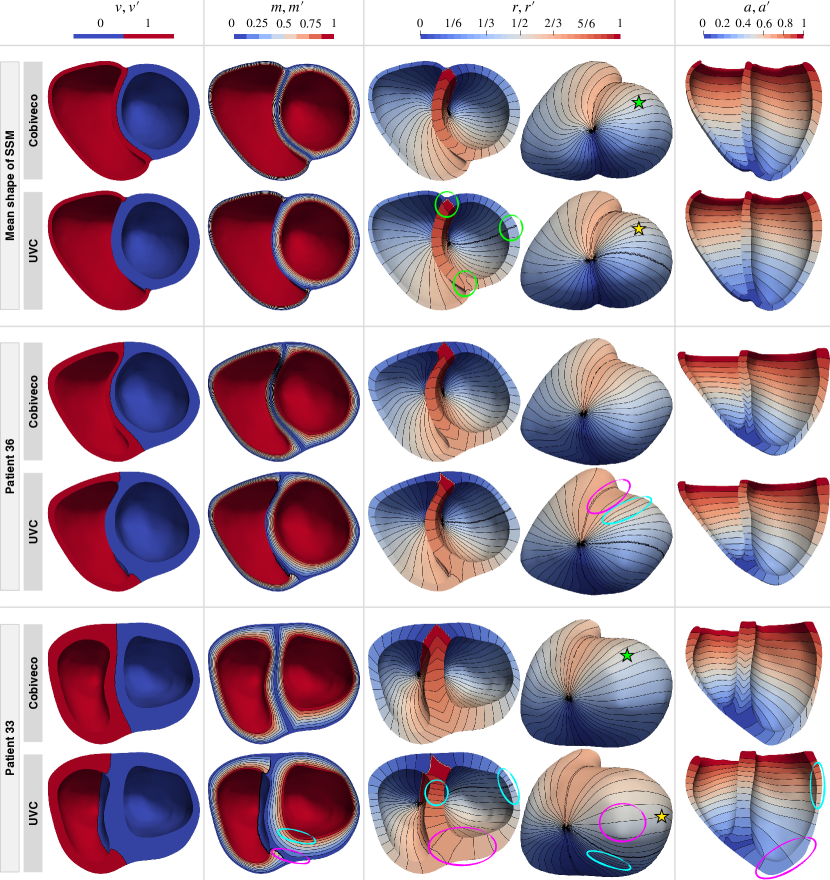

4.2 Visual comparison

Fig. 14 provides a visual comparison of Cobiveco and UVC for all four coordinates on the mean shape of the SSM and two exemplary patient geometries.

As the mean shape has a very uniform wall thickness, the contour lines of the rotational and apicobasal coordinates appear equidistant for both methods, but artifacts at the discontinuities of the rotational coordinate can be seen for UVC (green circles).

Patient 36 also has a relatively uniform wall thickness, but differences between both methods become more apparent. For UVC, the distance between contour lines of the rotational coordinate increases near the septal junctions (magenta vs. cyan circle), which is not the case for Cobiveco.

In patient 33, the differences are most pronounced. While the coordinates computed using Cobiveco still change very uniformly in space, there are substantial distortions in the UVC coordinates. The length of the segments between contour lines of the rotational coordinate changes up to four-fold between regions of small and large wall thickness. The apicobasal coordinate is also distributed very non-uniformly, indicating that the geodesic approach to normalize the apicobasal Laplace solution does not work reliably. In fact, a slight change of the geometry can cause a different geodesic path between apex and base to become the shortest and therefore lead to an abrupt change of the apicobasal coordinate. Taking a closer look at the transmural coordinate within the LV shows that it changes much faster at the endocardium than it does at the epicardium because the width of the region between the two boundary surfaces increases with the circumference.

If the coordinates always showed the same distortions for every geometry, this would only be a minor problem. However, comparing the rotational and apicobasal UVC coordinates for patient 33 and the mean shape reveals that the same coordinate values can represent quite different anatomical regions (yellow stars). In contrast, the coordinates obtained using Cobiveco are consistent across the geometries (green stars).

For pictures showing Cobiveco and UVC coordinates on all 36 patient geometries, the reader is referred to Fig. S1 and S2, respectively.